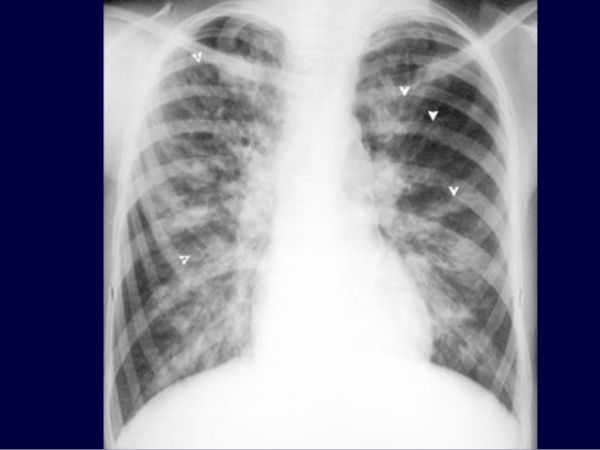

Giãn phế quản dạng ngón tay đi găng

Giãn phế quản có thể được phân loại thành các hình thức sau đây về hình thái (cả ba hình thức có thể có mặt trong cùng một bệnh nhân):

- Giãn phế quản hình trụ: phế quản được mở rộng và hình trụ.

- Giãn phế quản suy mạch: hình phế quản là không thường xuyên với các khu vực rộng và thắt.

- Hình túi hoặc nang: giãn phế quản dạng cụm nang. Đây là hình thức nghiêm trọng nhất của giãn phế quản và thường được tìm thấy ở những bệnh nhân bị xơ nang.